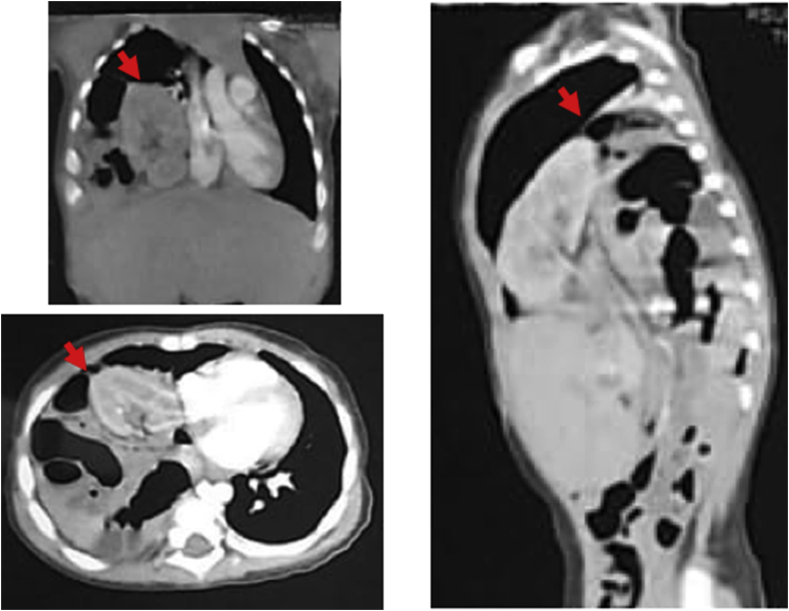

Two weeks after surgery, the patient suffered from respiratory distress again. Then, computed tomography (CT) scanning was conducted and revealed right diaphragmatic elevation and an ectopic kidney inside the right hemithorax (Fig. 2A). At 20 days after the first surgery, we performed the second surgery. During the operation, there was no longer elevation of the right diaphragmatic dome nor any other organ displacement (Fig. 2B). Moreover, we decided to let the intrathoracic kidney remain in place. Meanwhile, the patient recovered uneventfully and was extubated at three days after surgery. The patient was discharged from the NICU at eight days after the second surgery. Total length of stay of patient was 30 days in the NICU and no any in-hospital complications were found.

Fig. 2.

A) Computed tomography (CT) scanning indicated right diaphragmatic elevation and kidney inside the right hemithorax. B) Intraoperative findings displayed neither elevation of right diaphragmatic dome nor any other organ displacement.